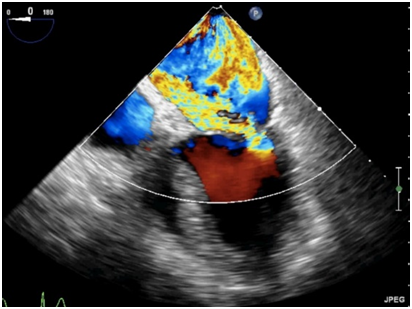

反流束的方向也很重要,其不仅仅是病因学的线索,也是严重程度的一个征象。中心性反流可由瓣环扩张或心室功能不全引起,偏心性反流(图19)常常由二尖瓣结构本身异常引起的,可认为出现偏心性的贴壁反流束属于中度以上反流[23]

什么叫超声容积探头围手术期经食管超声心动图监测操作的专家共识(可下载)_https://www.jmylbn.com_新闻资讯_第81张

图19偏心性二尖瓣反流食管中段四腔心切面二尖瓣彩色多普勒血流成像,可见重度MR沿左房内侧壁走行达心房顶部。